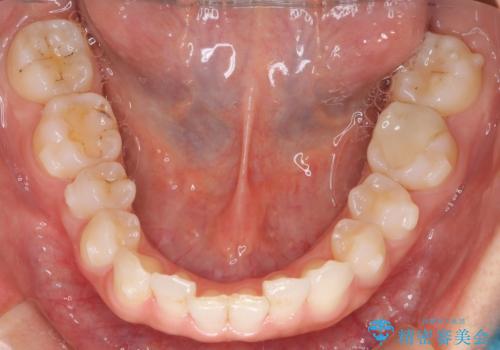

- 前歯のガタガタを主訴に来院されました。

叢生の量は軽度でしたが臼歯の遠心移動を行い、インビザラインにて治療をしました。

叢生の改善に必要なスペースは遠心移動やIPRで作ることが可能です。今回は遠心移動をメインにスペースを作って叢生の改善を行いました。